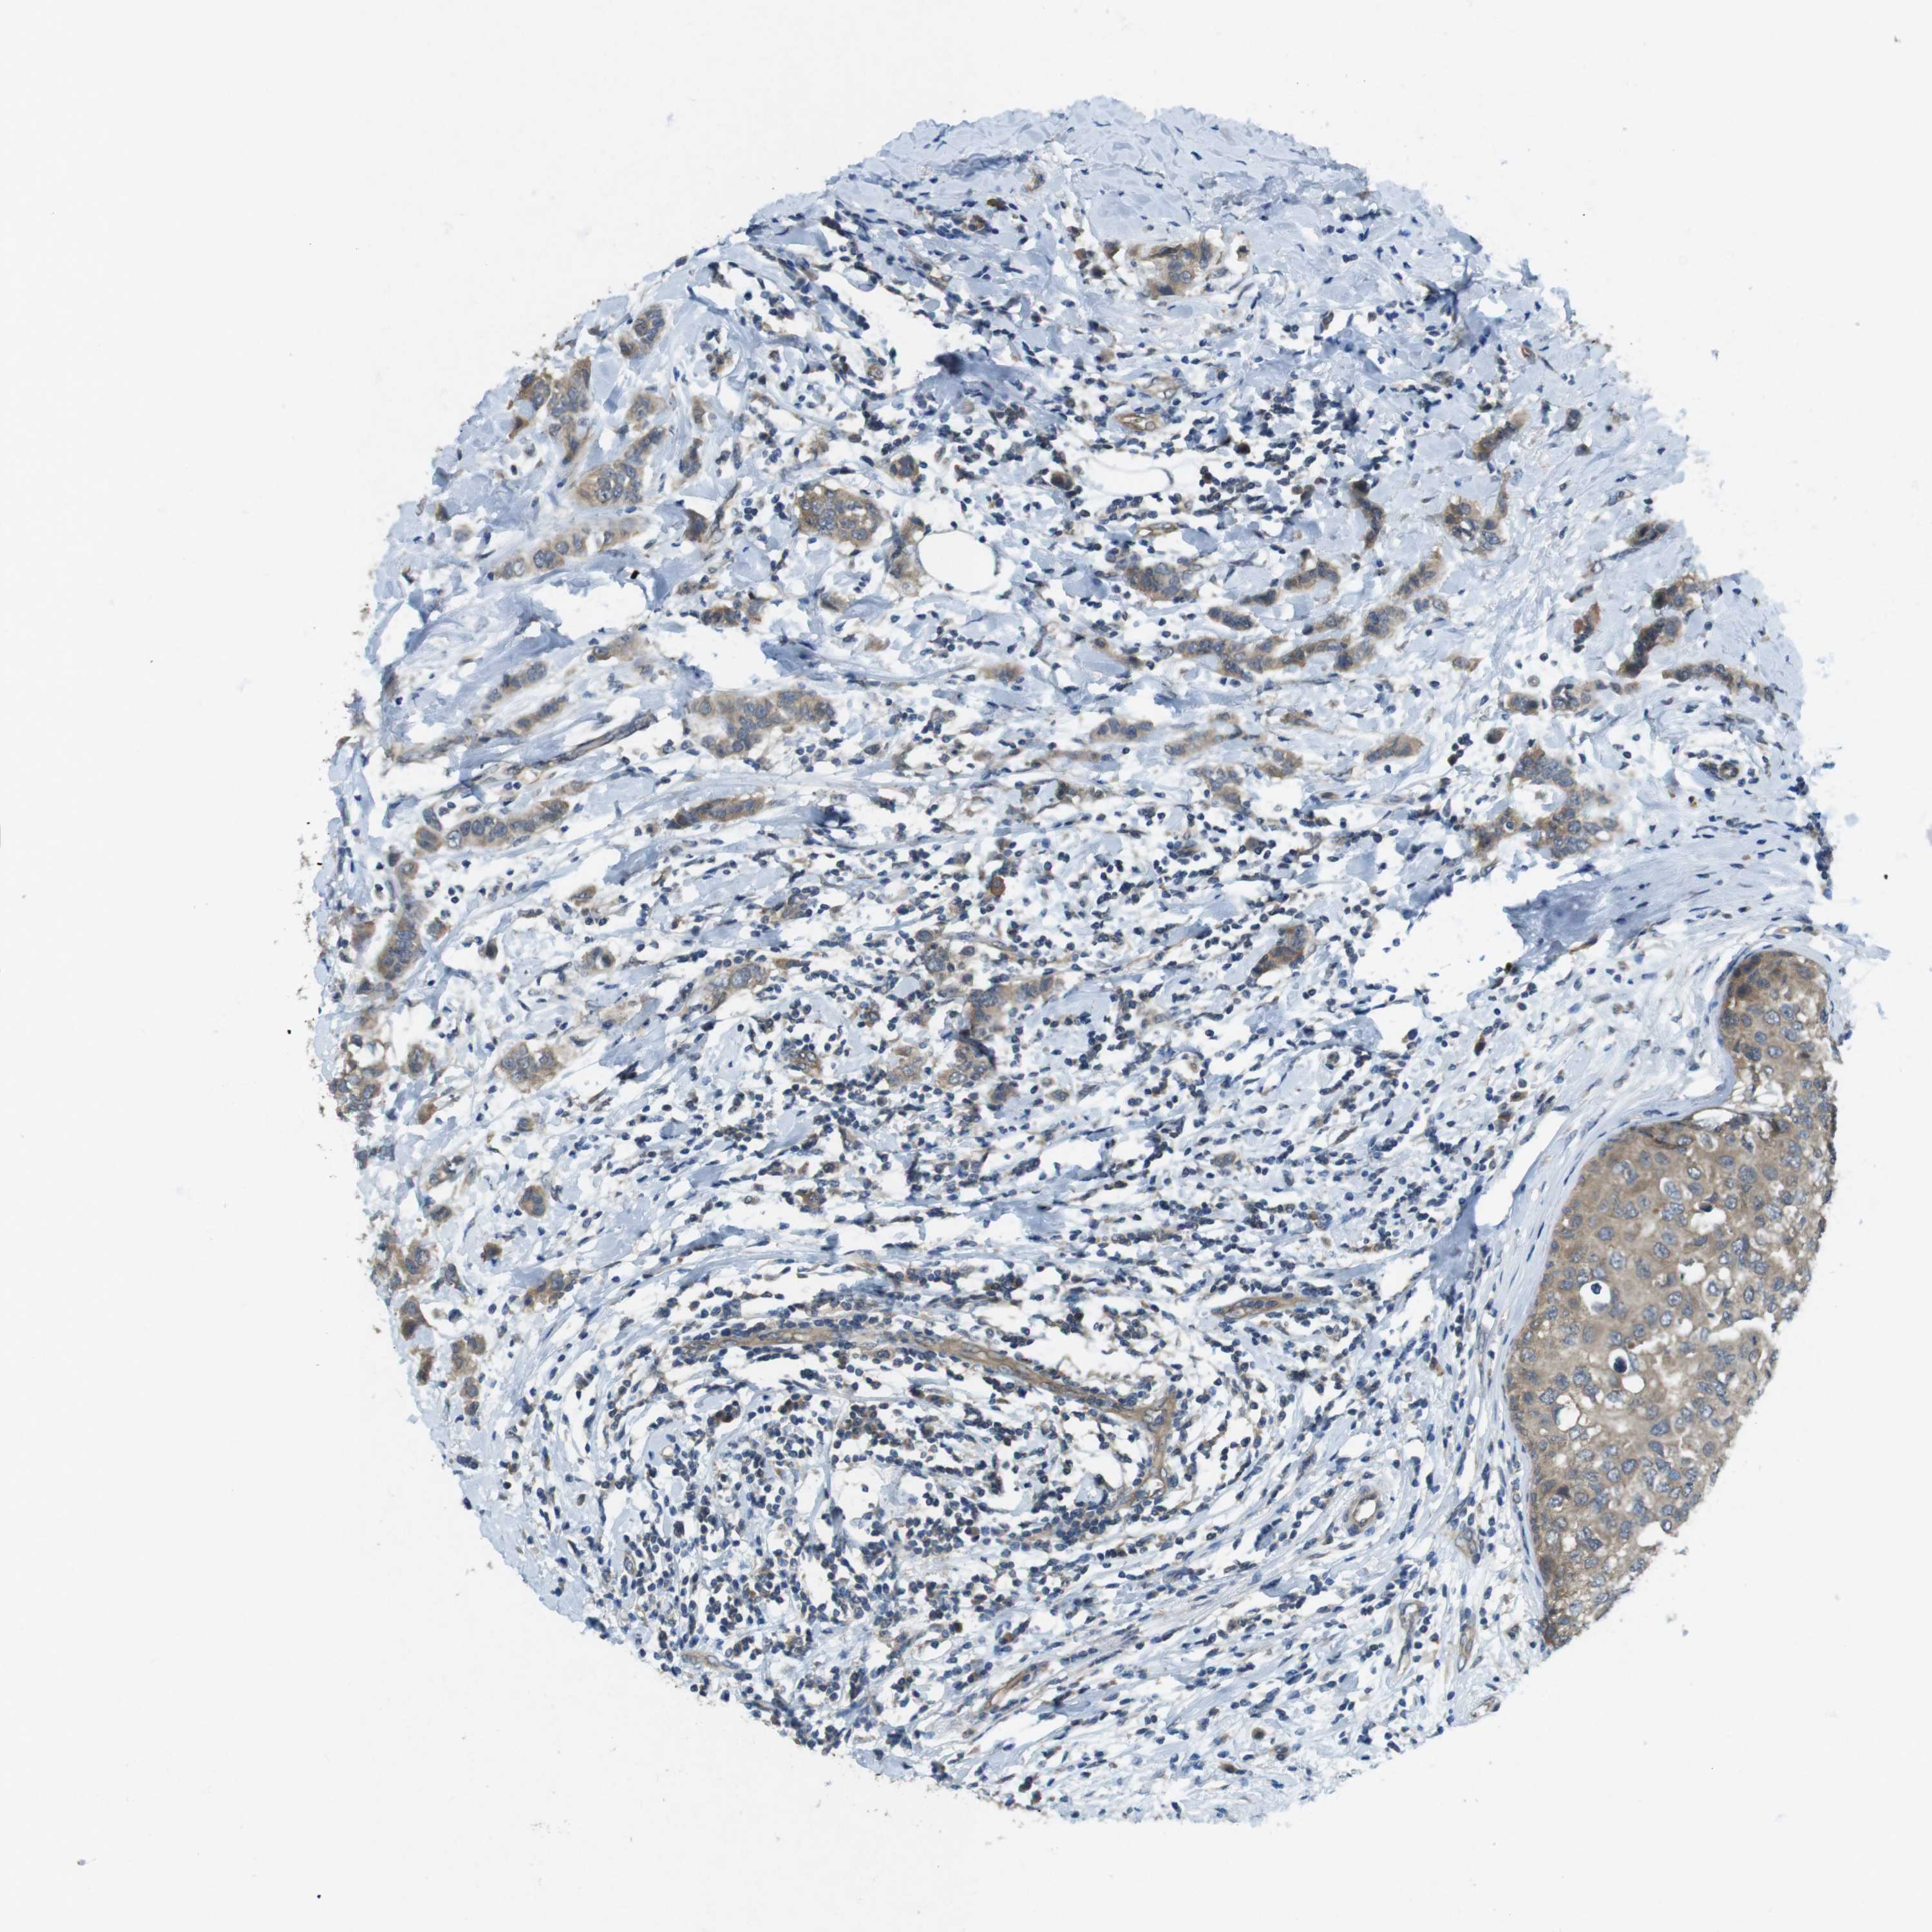

BRCA TCGA BRCA VALIDATION PROTEIN EXPRESSION